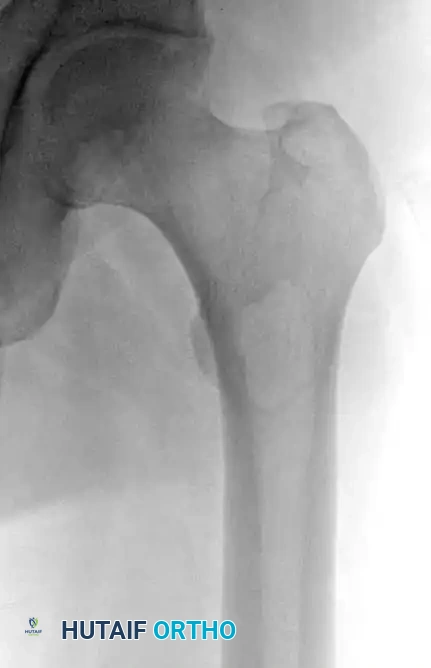

Fig. 20-19: (A) Intraosseous lipoma in the left proximal femur of a 51-year-old man. (B and C) The lesion demonstrates the same signal characteristics as normal macroscopic fat on both T1- and T2-weighted MRI sequences.

Radiographically, the appearance varies depending on the stage but generally maintains benign characteristics. They typically present as well-defined, geographic lucencies, often bordered by a thin, sclerotic rim of reactive bone.

Intraosseous lipomas undergo a well-documented evolutionary process, often categorized by the Milgram classification. Early-stage lesions consist of viable adipose tissue, while later stages exhibit central necrosis, cyst formation, and dystrophic calcification due to localized ischemia.

Advanced imaging is highly specific. Computed Tomography (CT) and Magnetic Resonance Imaging (MRI) reveal well-defined lesions exhibiting the exact signal characteristics of macroscopic fat (hyperintense on T1, suppressing on fat-saturated sequences). Central necrosis or targetoid calcification is frequently evident, representing infarcted adipose tissue. Because imaging is usually pathognomonic, a diagnostic biopsy is rarely necessary.